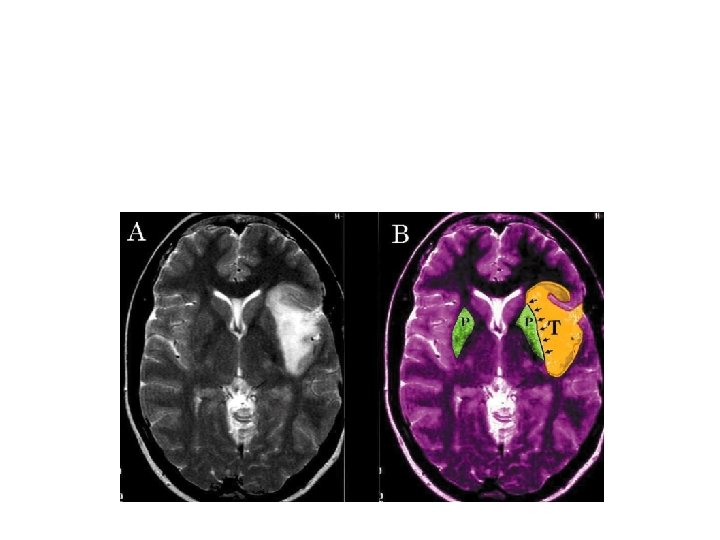

T 2 sharp imaging on benign tumor M. G. Yasargil, Ali F. Krisht, Ugur Ture, Ossama Al-Mefty and D. C. H. Yasargil Microsurgery of insular glioma Part III – Contemporary Neurosurgery 24; 13: 1 -6 Y. A. Moshel, J. D. S. Marcus, E. C. Parker and P. J. Kelly Resection of insular gliomas: the importance of lenticulostriate artery position. Clinical article. JNS November 2008; 109: 5

Lesion displacing LSAs medially often represent a sharp-well demarcated T 2 MR images and LGGs histology. On 429 Limbic-Paralimbic tumors 31/191 of the Insular Gliomas demostrated anaplastic grade (MG Yasargil Microsurgery of the insular gliomas on Cont. Neurosurg. VOL. 24, 14: JUL 15. 2002) Tumor with moderate shift of the LSAs and T 2 MR images showing a diffuse boundaries pattern are most likely HGG and aggressive surgery is often associated to permanent deficit.